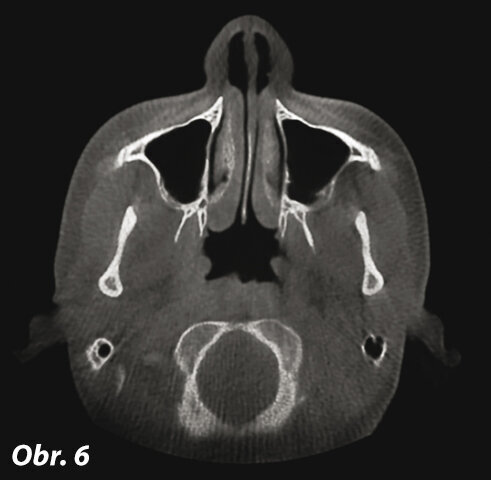

Transverzální rovina (obr. 5, 6)

Transverzální rovina je rovnoběžná s podlahou a okluzní rovinou. Rozděluje lebku na dvě stejné části: superiorní a inferiorní. Umožňuje prohlížet struktury směrem dolů a nahoru.